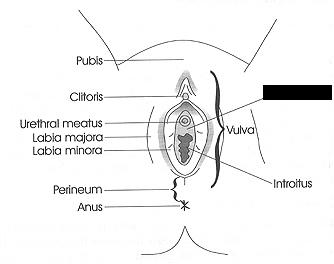

Clitoris

Labia majora/minora

Prepuce (=clitoral hood)

Vaginal orifice

Vestibule (of vulva)